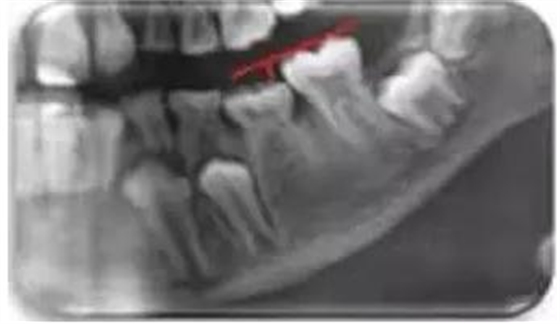

為了評估每次X線檢查的結(jié)果是否一致,檢查者和評估者采用相同的標(biāo)準(zhǔn)及標(biāo)準(zhǔn)化技術(shù),在不了解分組的情況下獨(dú)立地收集數(shù)據(jù)。系統(tǒng)地評估了組內(nèi)和組間檢查者的一致性。樣本包括472名兒童,分為3個(gè)年齡組:組1, 3-5.9歲,組2,6-9.9歲,組3,10-13年。本研究僅評估下頜乳磨牙。低牙合的程度通過使用精密計(jì)量器和毫米尺來測定,參考由作者改進(jìn)過的Bjerklin和Bennett法,在評估牙弓兩側(cè)時(shí),確定了最遠(yuǎn)端、完全萌出的磨牙、恒磨牙、第一磨牙、第二磨牙的咬合面作為參照(圖1)。

圖1 用一條垂直線畫在從低位磨牙的咬合面到第一顆恒磨牙的咬合面之間來測量低牙合程度。

低牙合的程度由從低位磨牙的咬合面到咬合面的垂直距離來判斷。距離小于1 mm忽略不計(jì),建立3級低牙合評分: 1.0 ~ 1.9 mm,輕度; 2.0至2.9毫米,中度;大于等于3毫米,重度。